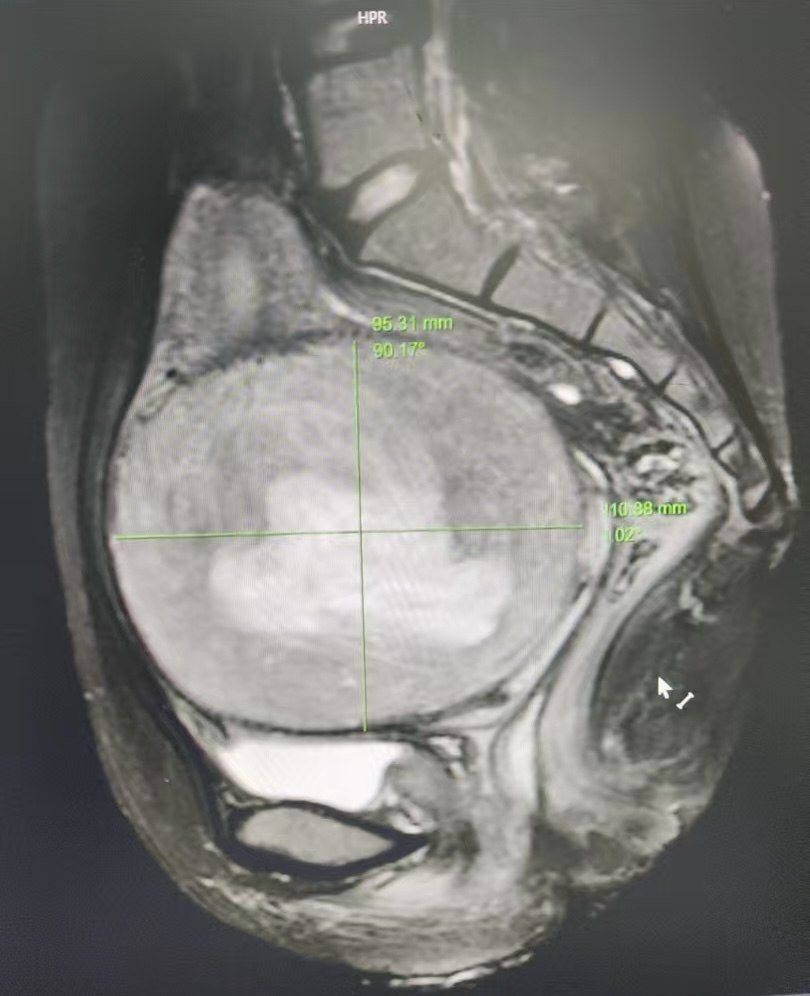

子宫肌瘤是女性生殖系统最常见的良性肿瘤,多见于30-50岁女性。若肌瘤生长过快或体积较大,可能导致月经量增多、经期延长、贫血等症状,严重时甚至影响生育功能。 病例回顾 近日,中山市神湾医院妇产科成功为一位因巨大子宫肌瘤导致月经过多,严重贫血的患者实施了腹腔镜下子宫肌瘤剔除术。 该女性患者34岁,近期月经量过多,来院检查发现子宫肌瘤大小约11cm,血红蛋白最低降至62g/L(正常女性≥110g/L),并出现乏力、头晕,活动后心慌等贫血症状。 图1 核磁下11厘米直径的大肌瘤 图2 腹腔镜镜下的子宫及子宫肌瘤 经团队评估,最终通过微创手术精准剔除肌瘤,术后恢复良好,贫血问题得到显著改善。 图3 术后子宫图片 医学科普 1.妇科腹腔镜手术适用范围 卵巢囊肿 子宫肌瘤 子宫内膜异位症 卵巢的良恶性肿瘤 子宫的良恶性肿瘤 宫外孕 不孕症等 2.腹腔镜手术的优势 1、创口小: 腹腔镜微创手术的创口非常小,只有几个小切口,相比传统手术的大切口,不仅美观,还减少了疼痛和感染的风险。 2、恢复快: 由于创口小,术后恢复时间大幅缩短...